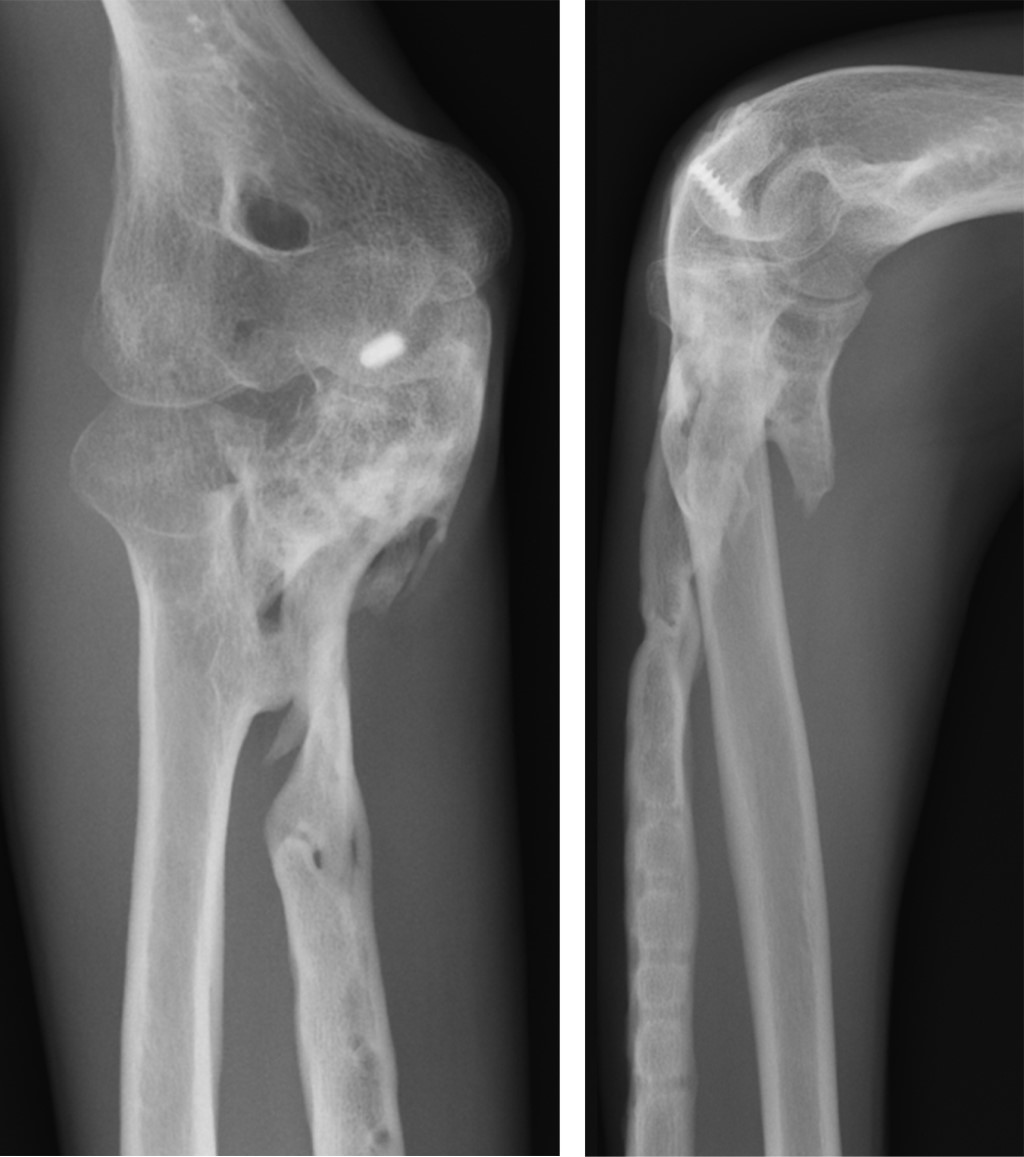

Un hombre de 39 años, drogodependiente en tratamiento con metadona, sufrió un accidente con el cual presentó una fractura luxación de Monteggia, abierta grado II de Gustilo y multifragmentaria de cúbito derecho (Figura 1). No había déficit nervioso.

De urgencia se realizó reducción cerrada de la cabeza radial y fijación provisional con dos agujas de Kirschner percutáneas, cierre de la herida, inmovilización con férula de yeso braquial y profilaxis antibiótica con cefalosporina. A los seis días se llevó a cabo la estabilización definitiva de la fractura mediante una placa de reconstrucción de titanio en el cúbito y fijación de la apófisis coronoides con un tornillo (Figura 2). El paciente no volvió a acudir a la evaluación tras ocho meses postoperatorios.